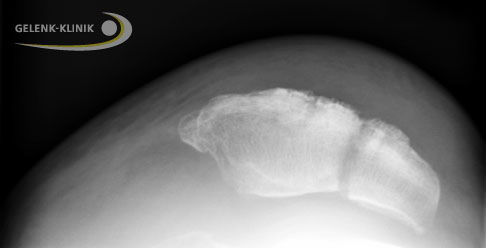

Zur radiologischen Diagnostik werden Röntgenbilder in 2 Ebenen der Patella angefertigt. In diesen kann die Art des Bruchs genauer beurteilt werden. Eine grobe Einteilung der Kniescheibenbrüche unterteilt Quer-, Längs- und Mehrfragmentbrüche.